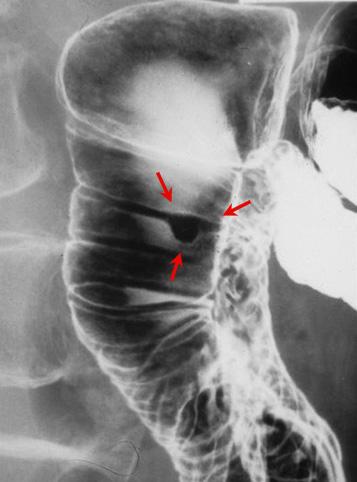

질환(병리주체)의 분류 양성 상피성종양/선종

부위(장기별) 십이지장/하행각

검사방법 X-P

종양의 육안분류 0형(표재형)/IIa형(IIa)

종양의 최대경(밀리미터) 1~9